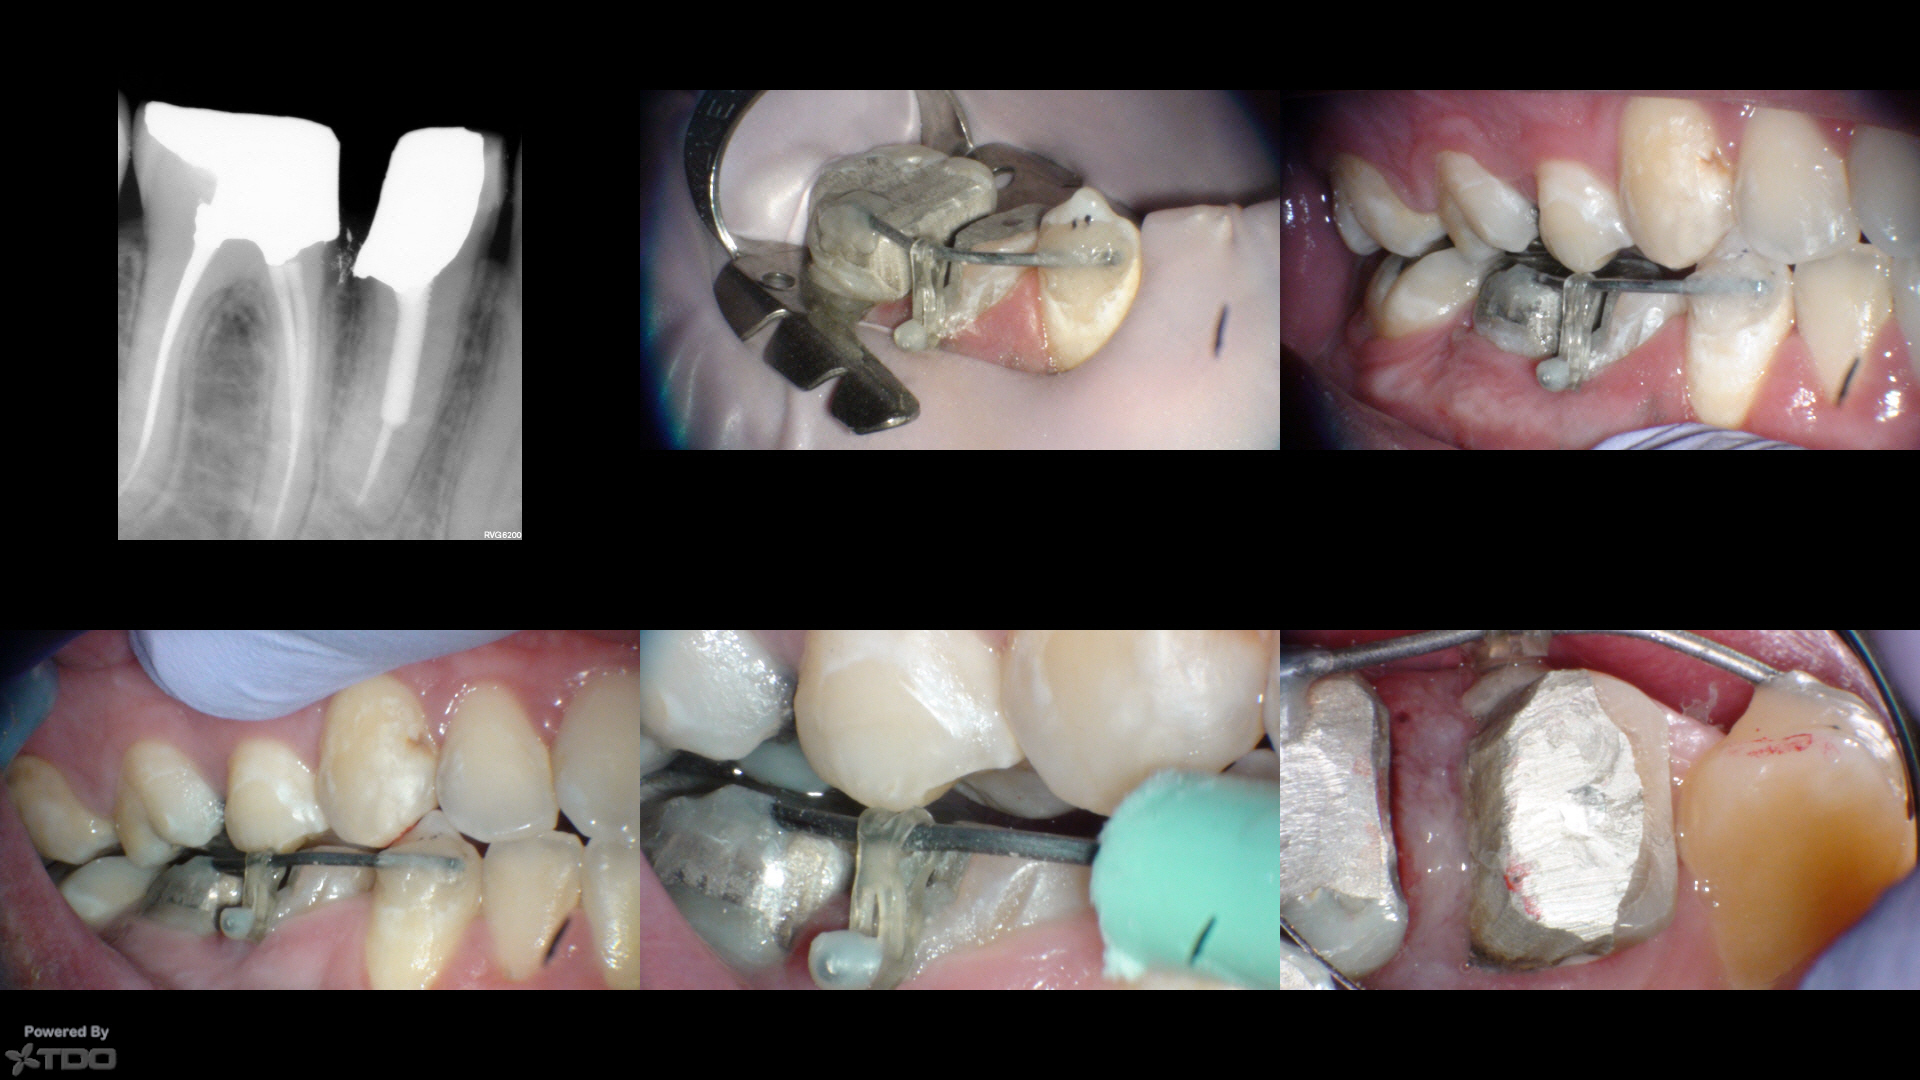

First ortho extrusion courtesy of Scott Weed.

Initially we were just going to punt on the bicuspid, but it was about 30 seconds to get the length and shape…so I just did it as I had the molar isolated.  Symptoms resolved, and with this fat root that is longer than it looks, I thought of Tom Cruise in Risky Business.  😀

(Yes, the amalgam is overhanging, I will fix that later)

I bored a couple of small holes in the amalgam on the occlusal of #30 and the cervical of #29 and had enough clearance on #27 to bond to the enamel.  I bent a paperclip with ortho pliers and stuck it #30 and bonded to #27 with Luxacore.  For #28, the tooth we want extruded, I put a wire in the cervical hole of #28 and made a little ball of resin on the sharp end (pics 2 and 3).  Check clearance and there were a few mm's for the tooth to move (not shown).

A week later, he comes in and the tooth has clearly moved (compare pic 3 to pic 4).  The P cusp of #4 was hitting the DL amalgam (pic 6).  We reduce #28 my a couple more mm's and checked clearance in CO (pic 5 is after reduction…sorry pic 5 and six are reversed in sequence).